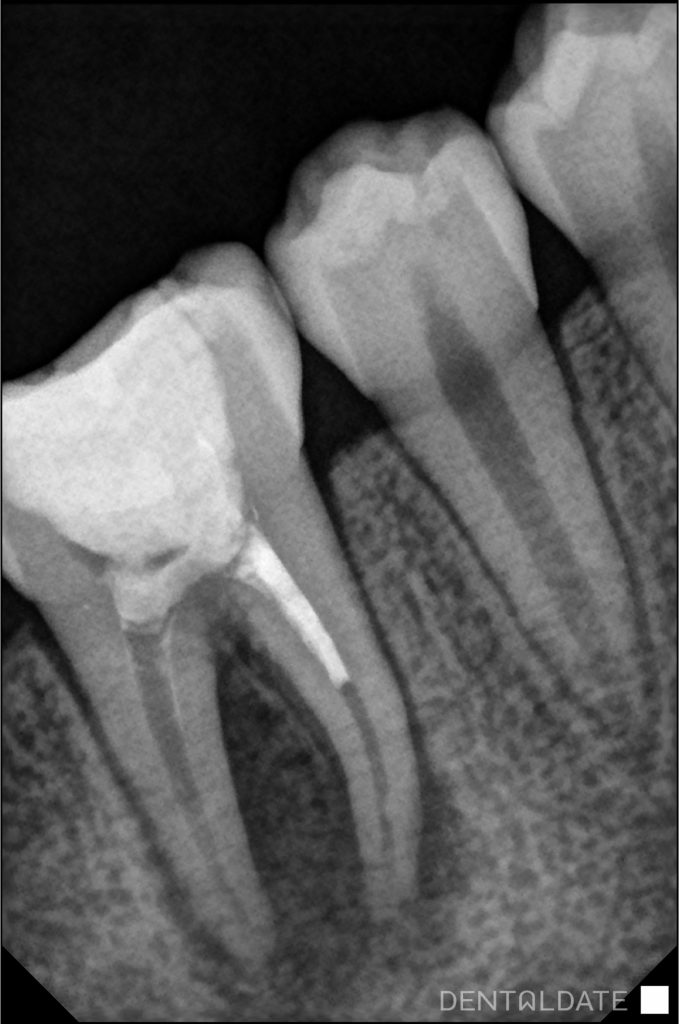

The canals are under-filled by 1/2 of the root length. The material in the canals is traced intermittently, pores inside. In the periapical tissues of both roots there is a focus of bone tissue loosening. Round shape, the contours are indistinct.

After a period of time the fistulous passage disappeared. A periapical photograph was taken, which showed a marked improvement of the rarefaction in the bone around the roots of the tooth.

The root canals were finally prepared and filled with hot compaction gutta-percha and AHplus siler. A hermetic filling was placed. Appearance for a control scan after 6 months.